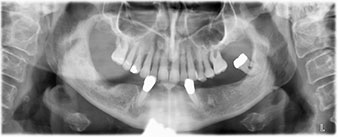

La paciente de 64 años se presentó con una dentición residual compuesta por las piezas dentales 38, 33 y 43 en el maxilar inferior y con una prótesis temporal fijada con ganchos en el maxilar inferior (figs. 1 y 2).

Para la planificación y la minimización del riesgo, se realizó una tomografía volumétrica tridimensional (TVD, Planmeca) que mostró que la calidad y la cantidad del tejido óseo era suficiente para la intervención quirúrgica y el tratamiento inmediato con el método Fast & Fixed. Siguiendo el protocolo de este método, se insertaron los implantes en la región de las piezas 35, 32, 42 y 45. Debido a la inclinación de hasta 45 grados de los implantes distales, el perfil de emergencia se desplazó hacia posterior y se generó un mayor polígono de soporte (fig. 3).